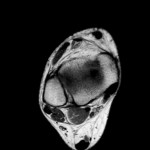

MRI Anatomy of the Elbow

Courtesy: Dr Jean Jose MD

Associate Chief Musculoskeletal Radiology Section

Associate Professor of Clinical Radiology

University of Miami School of Medicine, Florida, USA